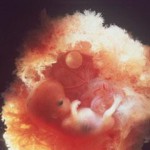

Tak wygląda płód w 11 tygodniu (klikalny):

USG w 11 tygodniu pokaże wyraźnie zarysy małego człowieka. Na wysokiej klasy sprzęcie ze szczególnie dobrą lokalizacją dziecka możesz już określić jego płeć. Jednak dane mogą być niedokładne.